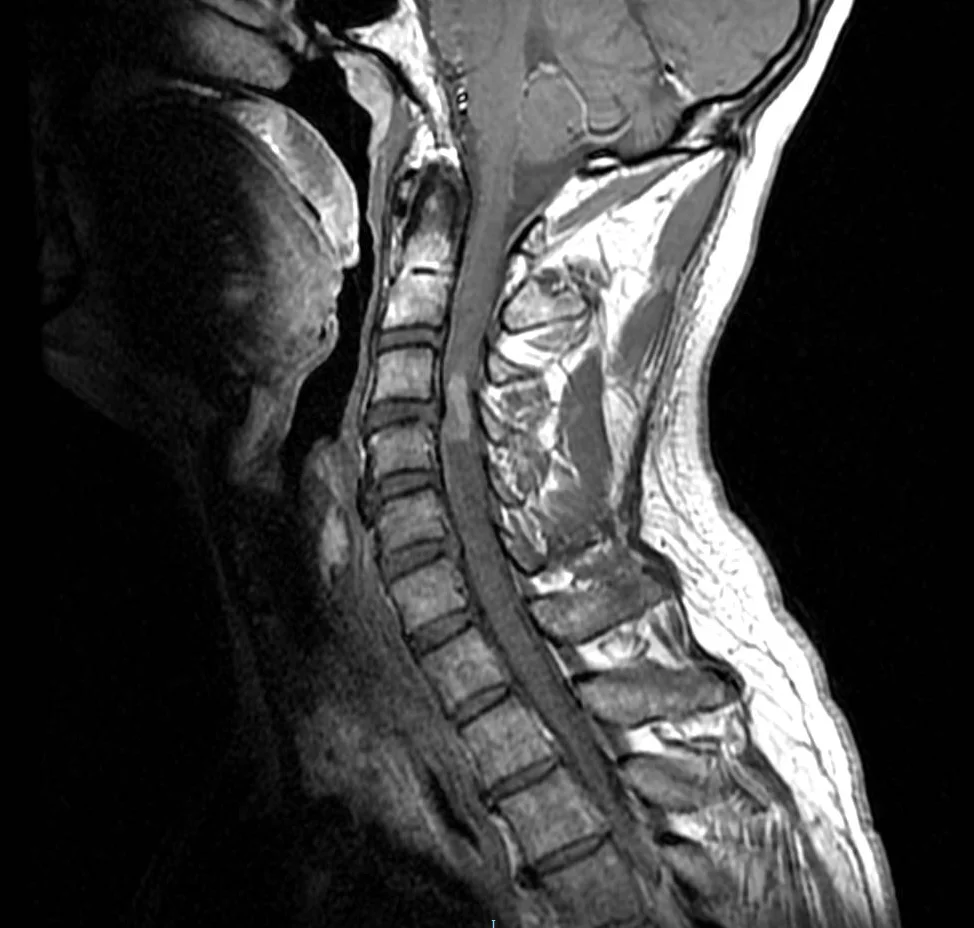

Le diagnostic est fait classiquement sur l’ IRM de la moelle épinière avec injection de Gadolinium. En fonction de la localisation et de l’aspect de la tumeur, votre neurochirurgien pourra vous demander de compléter ce bilan par un scanner et/ou une artériographie médullaire, qui pourra être organisée dans le service de Neuroradiologie interventionnelle situé dans le bâtiment Babinski (Pr Clarençon).